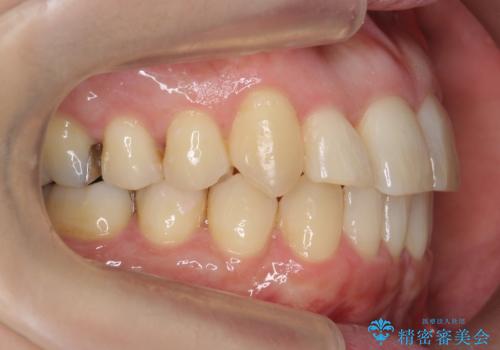

- 審美装置

- 2年3ヶ月

矯正用のミニスクリューを使用し、また、前歯をIPRすることで正中の左へのずれを最小限に抑えています。

上の前歯が内側に入っているクロスバイトは、笑った時に影になってしまい、かなり目立ちます。

内側に入っている前歯を外に出すだけで劇的に印象が変わります。